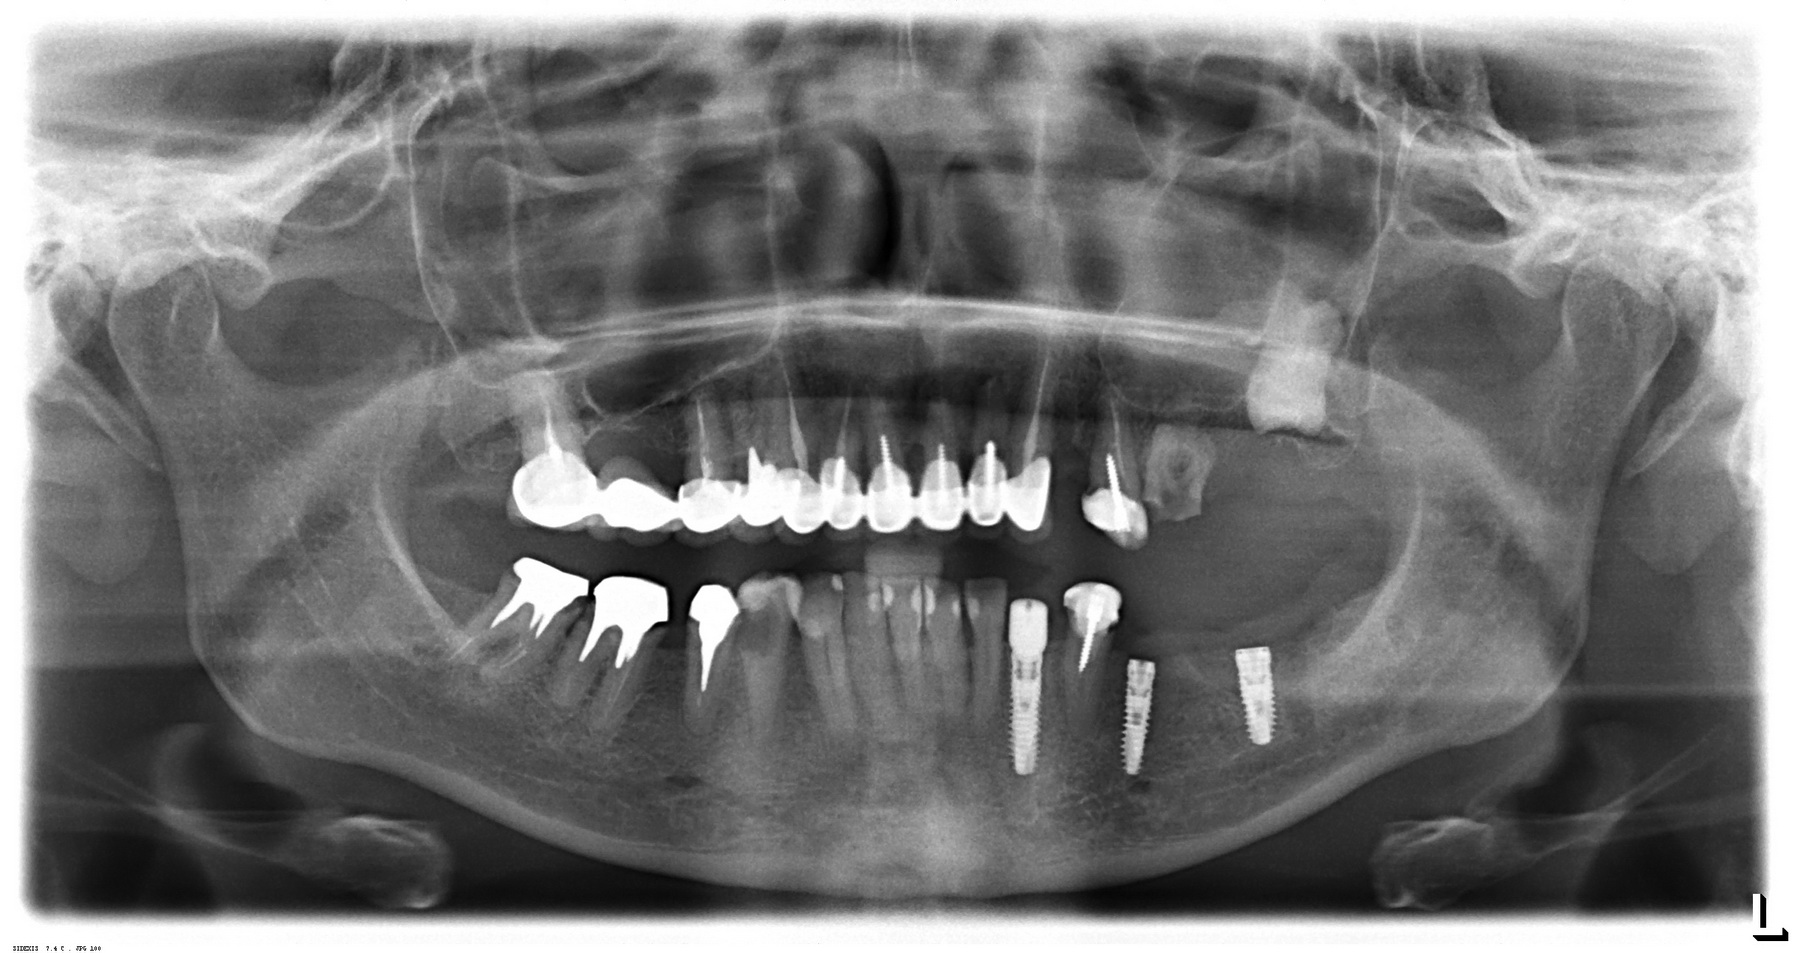

Вот пример. На этот раз, на снимках: пациентка, возрастом чуть больше сорока лет. После диагностики и необходимых исследований стало ясно, что необходимо хирургическое лечение во всех участках зубного ряда. В частности, удаление 13 зубов, включая ретинированный зуб мудрости, остеопластика на нижней челюсти и синуслифтинг, пластика слизистой и много чего еще.

У меня нет ипотеки и других долгов, поэтому я принимаю решение разбить весь объем хирургического лечения на четыре этапа — по одному в каждом из сегментов зубного ряда. И начинаю я… угадайте, с какого участка? Верно, с того, который уже не функционален из-за критического разрушения зубов — с левого нижнего:

Операция заняла всего 60 минут, послеоперационные явления были настолько незначительны, что пациентка чуть ли не через пару недель решилась на вторую операцию: